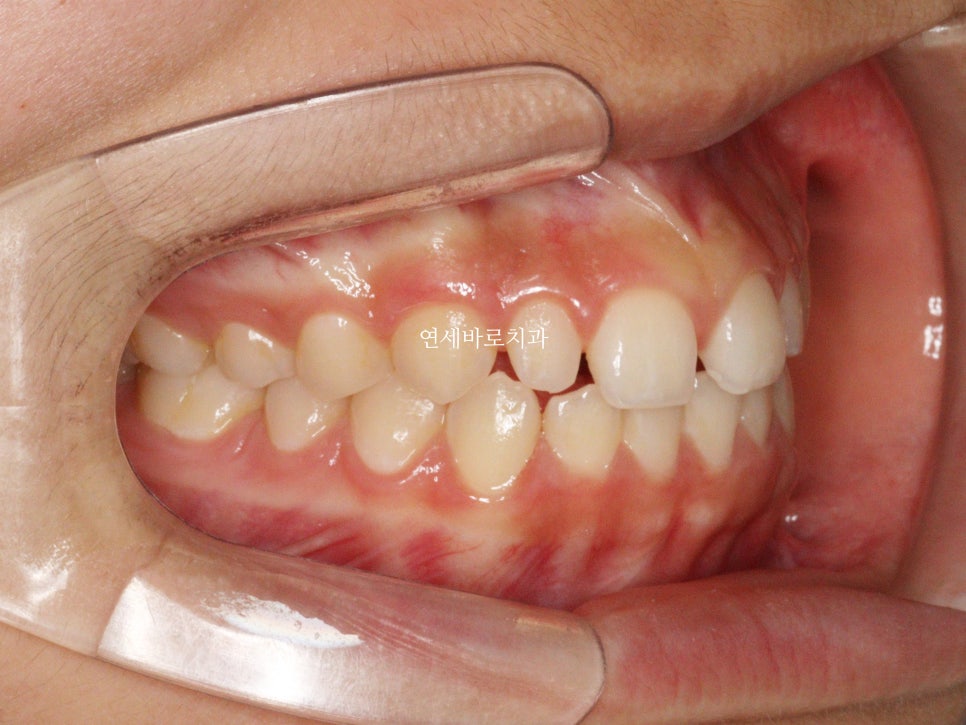

1월에 왔던 아이입니다. 어금니 교합은 너무나 좋아서 건들일것이 없었어요

앞니만 부분교정으로도 충분했습니다.

처음 치료를 시작한 날의 모습입니다.

치료가 끝난 당시 모습입니다.

앞니가 듬성듬성 벌어진것이 보기 아쉽네요

이렇게 된 이유는 두가지

왜소치

앞니 형태가 항아리모양 (네모가 아님)